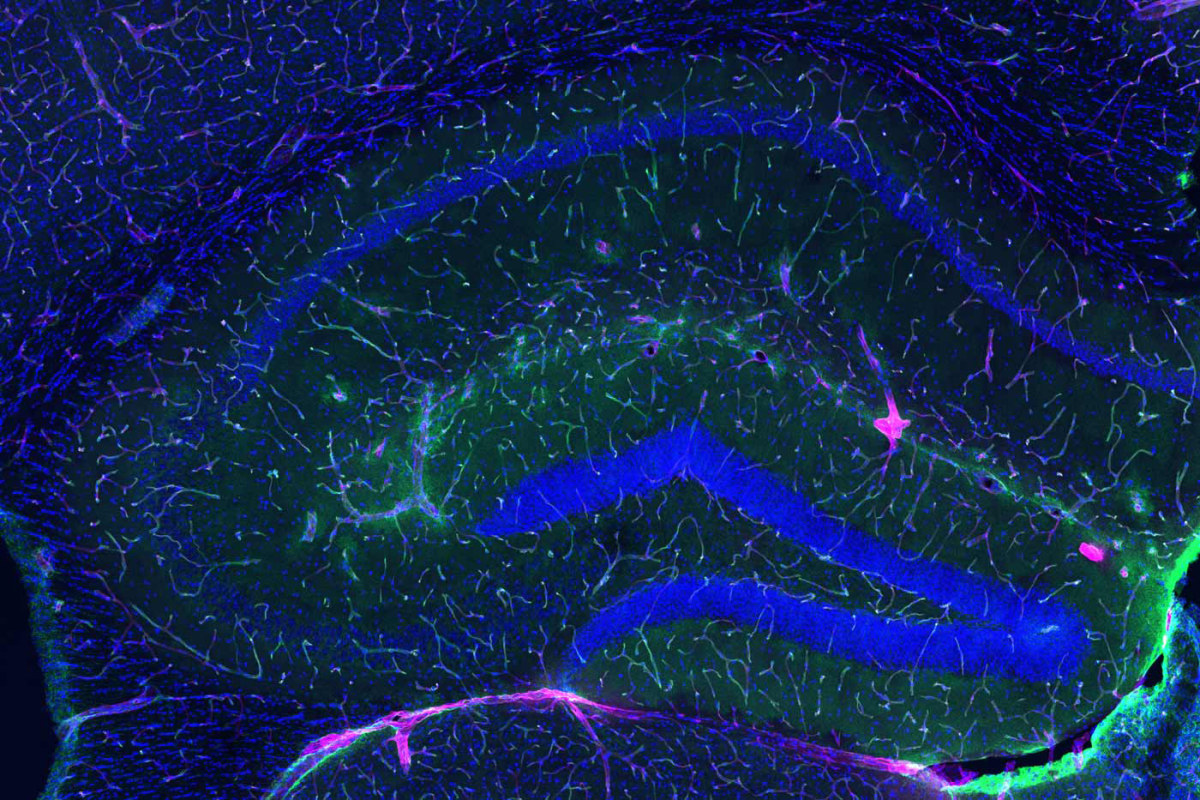

Para comprender la magnitud de este descubrimiento, debemos asomarnos a la microanatomía de la frontera cerebral. La BHE es una interfaz vascular altamente selectiva que separa el cerebro de la circulación sistémica, formada por un mosaico celular inexpugnable: células endoteliales microvasculares cerebrales (BMEC), astrocitos y pericitos.

A diferencia de otros vasos sanguíneos, las BMEC carecen de poros o fenestraciones. Están selladas por uniones estrechas (compuestas por proteínas como claudinas y ocludinas), que restringen severamente el paso de sustancias, permitiendo solo la entrada de nutrientes esenciales y orquestando la expulsión meticulosa de neurotoxinas como el amiloide-beta.

La restauración de las murallas

El estudio definitivo de 2026 resolvió el enigma demostrando que la GPLD1 no necesita entrar al santuario para protegerlo; libra su batalla en la periferia. Impulsado por el ejercicio, el hígado vierte GPLD1 en la sangre. Al alcanzar los vasos cerebrales, esta enzima actúa como una “tijera molecular” que recorta y libera a la perjudicial TNAP, arrancándola de las paredes vasculares.

Los resultados son asombrosos. Al administrar GPLD1 a ratones geriátricos (equivalentes a humanos de 70 años), la arquitectura de la barrera se restauró instantáneamente. La neuroinflamación se extinguió y los animales recuperaron una memoria y agilidad mental propias de su juventud.